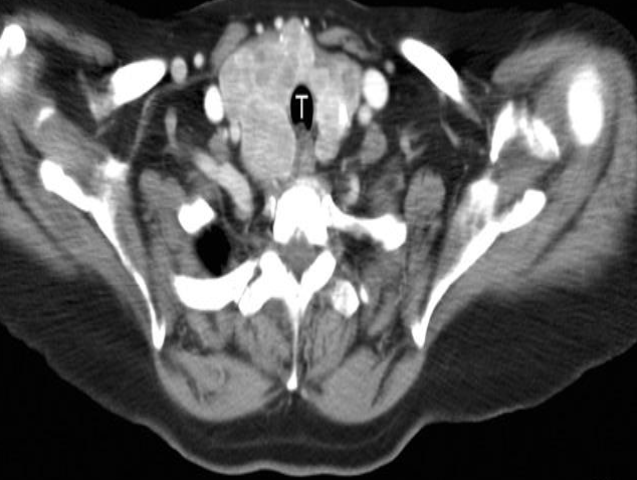

MALE REPRODUCTIVE SYSTEM IMAGING

Scrotal US - A hydrocoele is demonstrated surrounding an otherwise normal testis .

A man presents with testicular atrophy and infertility

Ultrasound of the scrotum Dilated pampiniform veins can be seen within the left scrotum. Doppler sonography (image b) shows the venous reflux. These findings are characteristic of varicocele.

Patient presented with scrotal pain

and swelling - Ranges from mild tenderness to a severe febrile process with acute unilateral scrotal pain. -

A. Give the name of imaging examination. Color Doppler ultrasound

B. Describe the abnormality imaging shows Reactive hydrocele and scrotal wall thickening , edematous epididymis and shows increase vascularity on Doppler

C. What is the most probable diagnosis in the ? Epididymitis

A. Give the name of imaging examination.

*Color Doppler ultrasound is the gold standard investigation.

B. Describe the abnormality

- Hypoechogenicity: Focal or diffuse

- Hypervascularity: Focal or diffuse

- Swelling - Scrotal wall thickening + Scrotal pain and swelling

C. What is the most probable diagnosis in the ? Orchitis

Color Doppler ultrasound of both testes (transverse plane) of a 14-year-old boy

B. Describe the abnormality woke up with acute right scrotal pain - The right testis shows intratesticular flow slightly reduced compared to the left testis

C. What is the most probable diagnosis ? These findings are consistent with testicular torsion

- Prostatic calcification

- symmetrical about the midline, are seen just inferior to the bladder